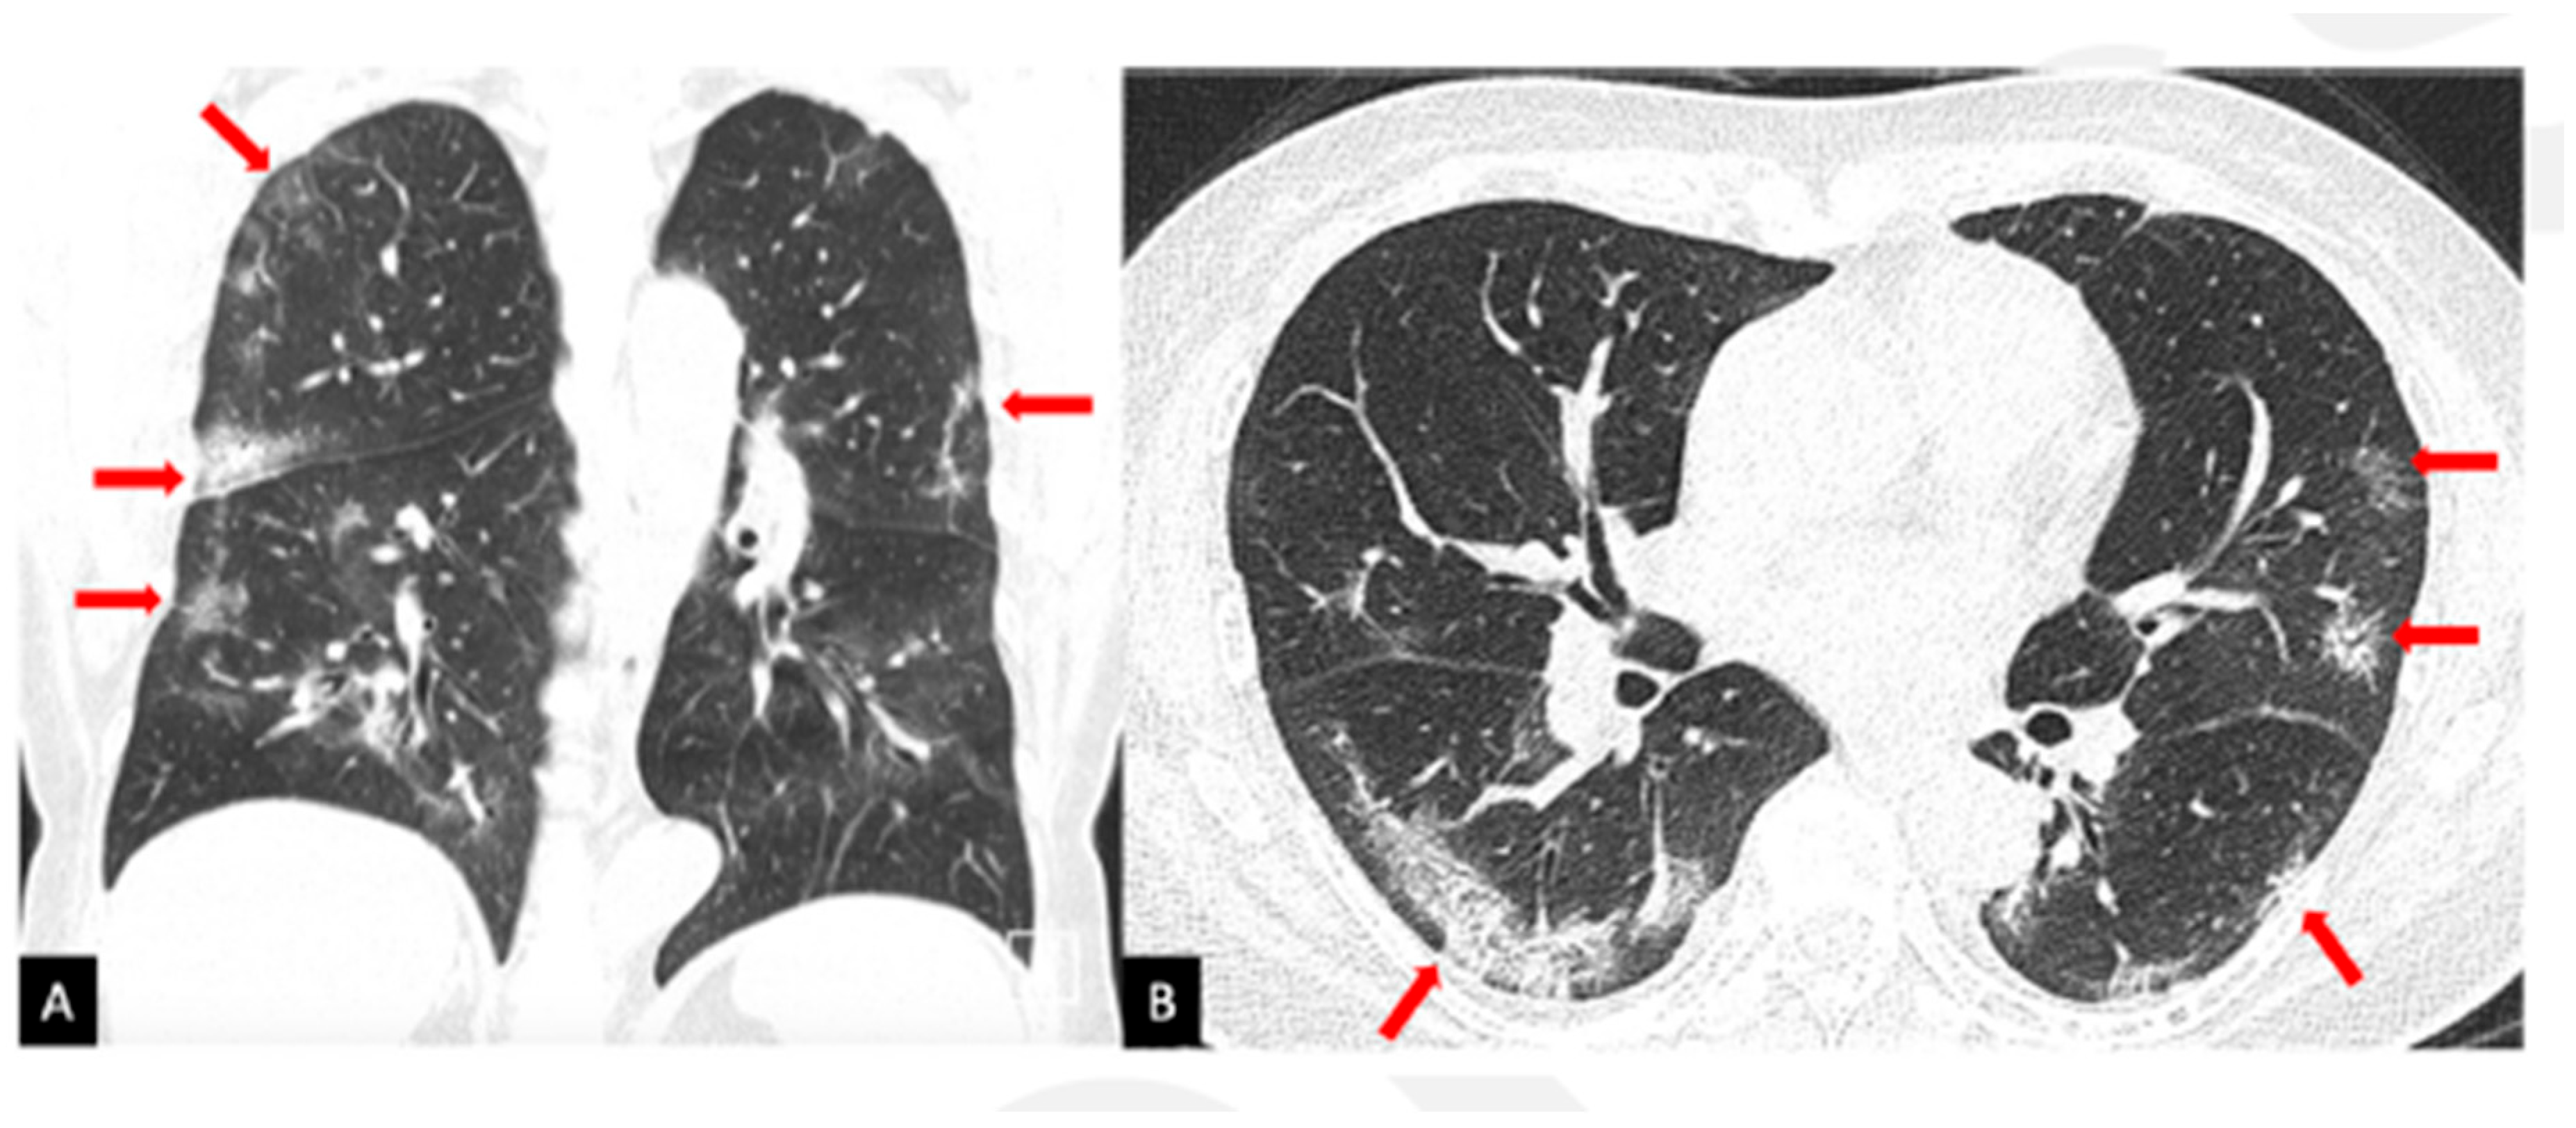

3.2. Case B

- Ng, M.-Y.; Lee, E.Y.; Yang, J.; Yang, F.; Li, X.; Wang, H.; Lui, M.M.-S.; Lo, C.S.-Y.; Leung, B.; Khong, P.-L.; et al. Imaging Profile of the COVID-19 Infection: Radiologic Findings and Literature Review. Radiol. Cardiothorac. Imaging 2020, 2, e200034. [Google Scholar] [CrossRef] [PubMed]

- Chung, M.; Bernheim, A.; Mei, X.; Zhang, N.; Huang, M.; Zeng, X.; Cui, J.; Xu, W.; Yang, Y.; Fayad, Z.A. CT imaging features of 2019 novel coronavirus (2019-nCoV). Radiology 2020, 295, 202–207. [Google Scholar] [CrossRef]